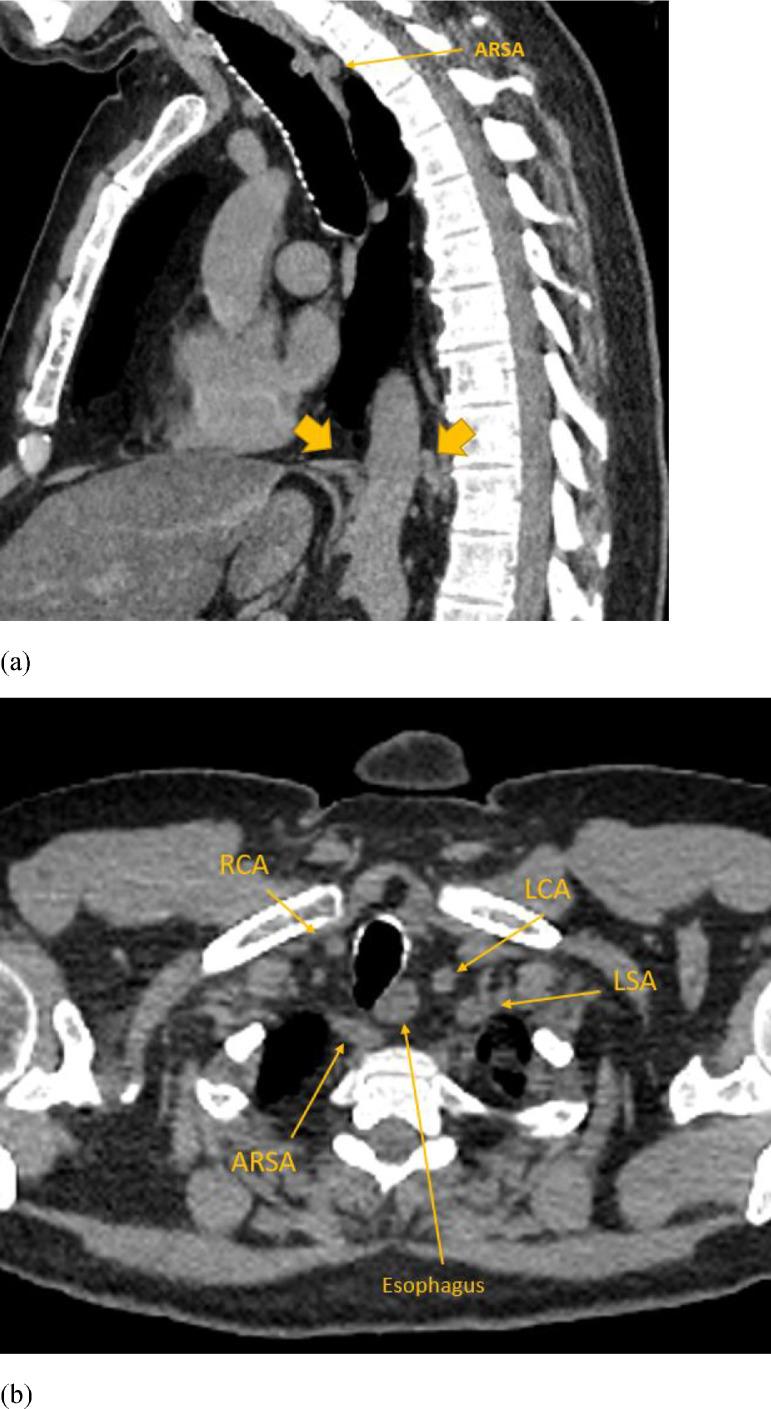

马蹄形肾上腺伴主动脉后右侧膈脚及多种血管变异:2例报告

Horseshoe adrenal gland associated with retro-aortic right diaphragmatic crus and several vascular variants: Report of two cases.

Horseshoe adrenal gland (HA) refers to congenital fusion of the adrenal glands across the midline - a rare anatomical variant often found in association with other congenital anomalies. Here we report 2 cases of HA associated with retro-aortic course of the right diaphragmatic crus, yet another rare anatomical variant, in a 61 your-old male and a 69-year-old female, who underwent CT examinations for unrelated reasons. Both patients also had additional vascular and vertebral anomalies. To the best of our knowledge, this is the first report to document association of 2 rare congenital anomalies: HA and retro-aortic right diaphragmatic crus.

摘要

马蹄形肾上腺(HA)是指肾上腺跨越中线的先天性融合——一种罕见的解剖变异,常与其他先天性异常相关。本文报告2例马蹄形肾上腺合并右膈脚走行于主动脉后方(另一种罕见的解剖变异)的病例,患者分别为一名61岁男性和一名69岁女性,他们因无关原因接受了CT检查。两名患者还存在其他血管和脊柱异常。据我们所知,这是首次报道两种罕见先天性异常:马蹄形肾上腺和右膈脚走行于主动脉后方的关联。